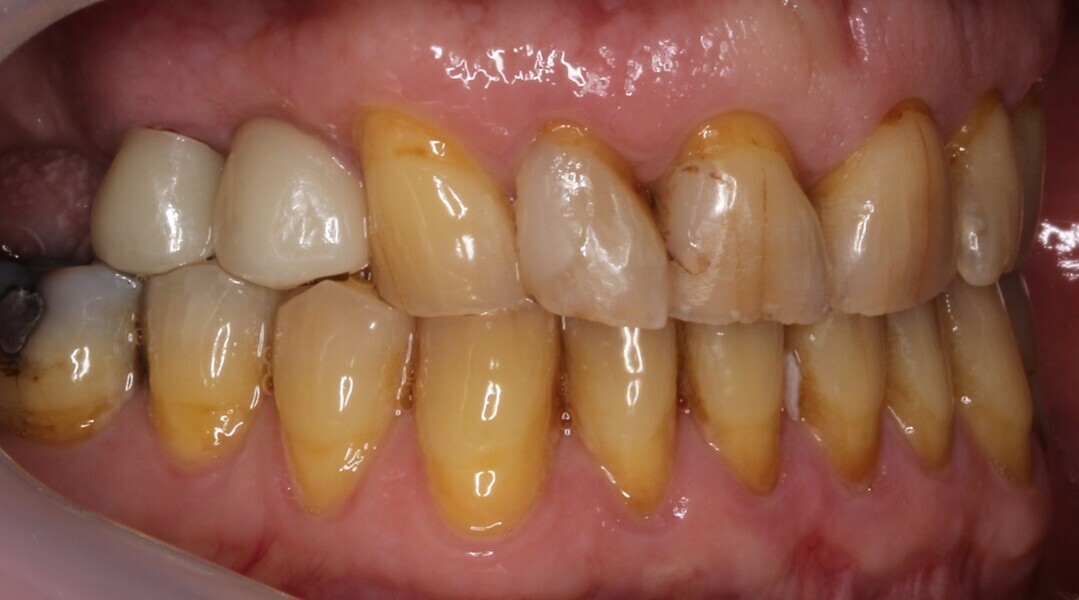

A waiting period of four months allowed adequate osseointegration of the implant (Fig. 20). The endodontic treatment of tooth #15 had been completed in the meantime, and the tooth had been prepared for a complete zirconia crown. Removal of the implant provisional restoration revealed a natural soft-tissue profile and an improved soft-tissue contour without the need for additional soft- or hard-tissue augmentation (Fig. 21).

Secondary impression was taken digitally with an intra-oral scanner and the relevant scan body. Definitive restorations were designed on exocad and milled in-house on CRAFT 5X (DOF) out of EVEREST Multilayer AT zirconia (Shade A3; UNC International). A deliberately lighter shade was chosen by the patient, as he intended to have the appearance of his other maxillary teeth improved. The implant crown was torqued in to 35 N cm, and the crown was cemented to tooth #15 using G-CEM ONE cement (GC Dental; Figs. 22–24).

Digital dentistry and novel techniques can help produce excellent and effective results. Improvements in the software and physical workflow have meant that the clinician’s and the technician’s work are not only more streamlined and straightforward but also enjoyable (Fig. 25). A more-than-satisfactory outcome was achieved for the patient. What made all this possible was the novel and innovative tissue-level matrix implant connection, which lacks any sharp corners or edges, allowing for direct-to-implant milled and printed restorations. Overall, 3D printing and software can unlock numerous applications to improve not only the patient outcomes but also the operator experience. It will be truly exciting to see the innovations that lie ahead.